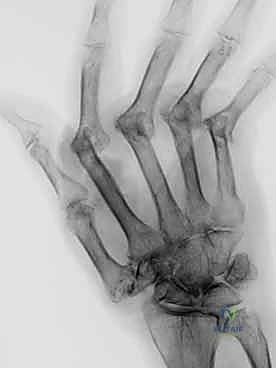

مع تقدم حالات التهاب المفاصل، وخاصة التهاب المفاصل الروماتويدي (Rheumatoid Arthritis)، يحدث تدمير تدريجي للغضاريف المفصلية والأربطة الداعمة، مما يؤدي إلى تشوهات قاسية وانحرافات مؤلمة في الأصابع (مثل الانحراف الزندي). في هذه المراحل المتقدمة، وبعد استنفاد كافة الحلول الدوائية والعلاجات التحفظية، تبرز جراحة استبدال مفصل اليد بالسيليكون كطوق نجاة حقيقي.

- المفاصل الرسغية السنعية (MCP - Metacarpophalangeal Joints): وهي المفاصل الكبيرة الموجودة عند قاعدة الأصابع (مفاصل برجمة اليد). هذه المفاصل هي الأكثر عرضة للتشوه بسبب الروماتويد، حيث تميل الأصابع للانحراف نحو الخارج (باتجاه عظمة الزند).

- المفاصل بين السلامية القريبة (PIP - Proximal Interphalangeal Joints): وهي المفاصل الوسطى في الأصابع. تلف هذه المفاصل يؤدي إلى تشوهات معقدة تُعرف طبياً بتشوه "عروة الزر" (Boutonniere) أو تشوه "عنق البجعة" (Swan Neck).

عندما يهاجم جهاز المناعة (في حالة الروماتويد) الغشاء الزليلي المبطن لهذه المفاصل، فإنه يتضخم ويدمر الغضروف الناعم الذي يسمح بانزلاق العظام بسلاسة، مما يؤدي إلى احتكاك العظم بالعظم، وهو ما يسبب الألم المبرح والتشوه.

2. استئصال المفصل التالف

باستخدام أدوات جراحية مجهرية دقيقة، يقوم الدكتور هطيف بإزالة رؤوس العظام المتآكلة والزوائد العظمية (Osteophytes) التي تسبب الألم وتعيق الحركة.